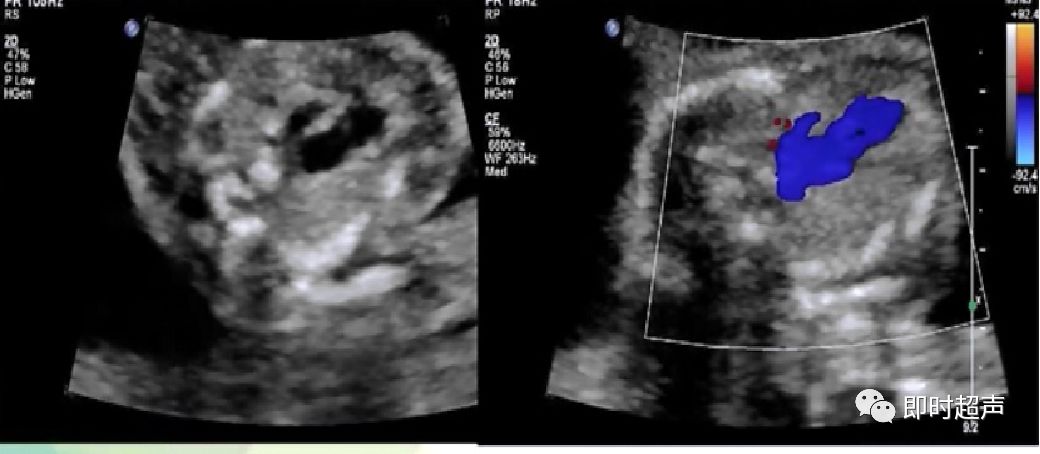

肺动脉瓣闭锁时肺动脉是否一定变细?

- 肺动脉不一定变细,因为肺动脉的血液是由主动脉经动脉导管来反向灌注的,只要动脉导管足够粗,肺动脉内径是可以不变细的。

- 但肺动脉的血流方向一定是和主动脉相反的。

- 所以诊断时不能依靠肺动脉的内径来判断有无肺动脉瓣闭锁。